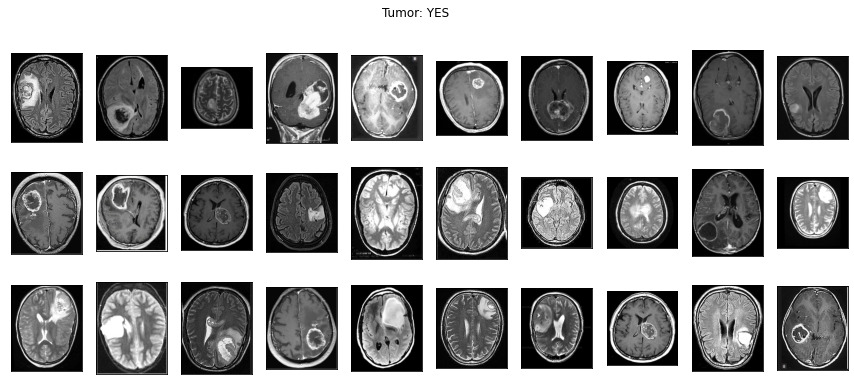

아울러 일반적인 사진 이외에 의료영상도 이미지 분석이 가능해요. 의료영상은 DICOM(Digital Imaging and Communications in Medicine) file(확장자 .dcm)로 저장되어 있어요. 'Digital' 즉, 숫자 형식으로 되어있기에 이미지 분석이 가능해요. 아래의 이미지는 뇌종양을 진단하기 위한 MRI 이미지예요!

이 이미지를 이용해서 뇌종양을 예측하는 알고리즘을 아래에서 실습해볼테니 끝까지 봐주세요!

네! 위에서 보았던 뇌종양 양성과 음성의 MRI 이미지 데이터로 뇌종양 진단을 한다면 아래와 같이 할 수 있어요.

양성 1500개, 음성 1500개인 균등한 데이터를 준비해서 <Image Reader>로 읽었어요. ‘yes’ 주석이 있는 윗줄이 양성 이미지이고 ‘no’ 주석이 있는 아랫줄이 음성 이미지에요.